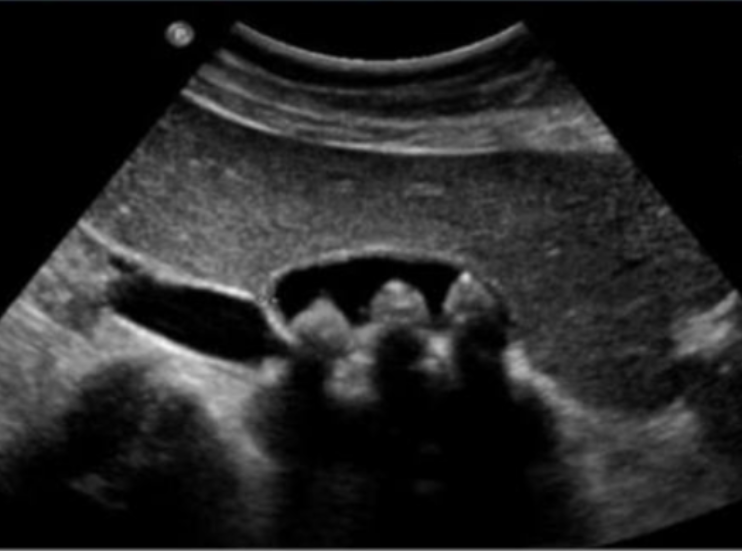

1- What is your diagnosis?

Chronic calcular cholecystitis.

2- Give 4 complications? -

- Pancreatitis. -

- Obstructive jaundice. -

- Gall bladder cancer. -

- Cholangitis

Acute Calcular Cholecystitis

U/S from patient with recurrent upper abdominal pain.

Diagnosis -

calculous cholecystitis

Four common complications

- peritonitis

- perforation

- choledocholithiasis

Gallbladder stone (calcular cholecystitis)

Complication:

- cholangitis,

- choledocholithiasis,

- pancreatitis,

- gallbladder perforation

Imaging technique:

- ultrasound

An ultrasound image from a patient with recurrent upper abdominal pain.

Q1: What is your diagnosis?

- Cholecystitis

Q2: Name FOUR common complications of this disease.

- Peritonitis,

- Perforation,